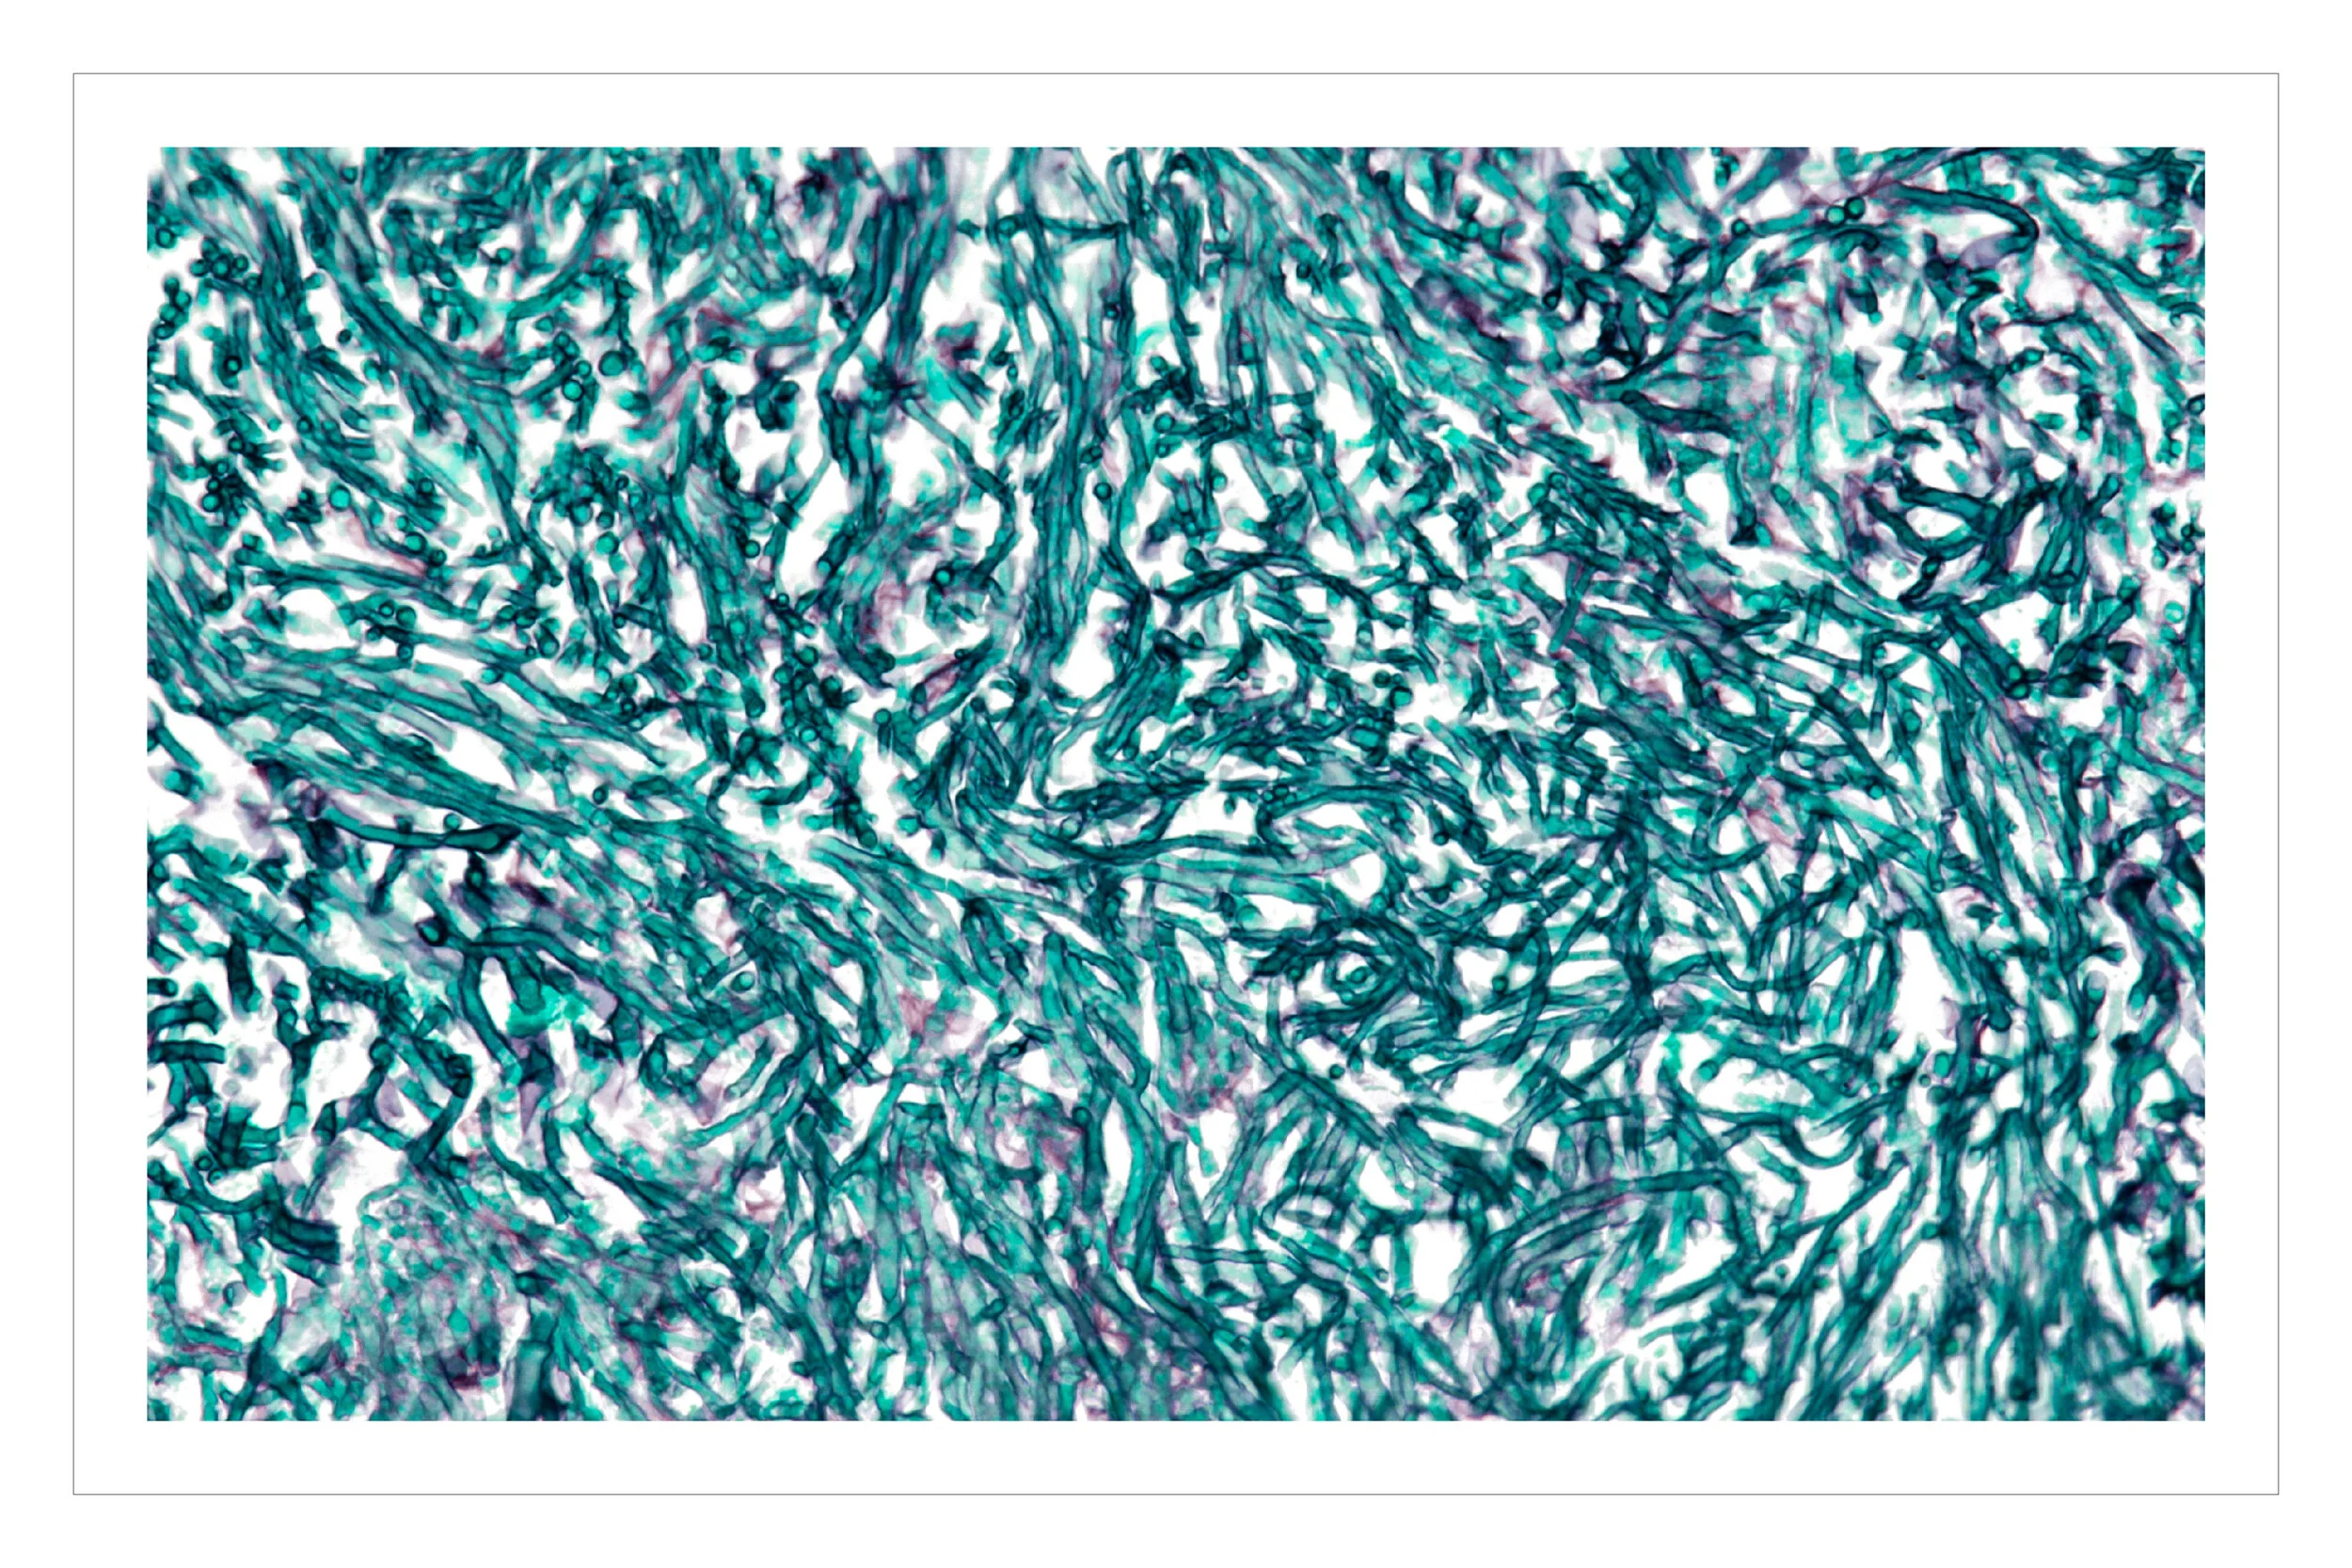

pathology images, with emphasis on the “special stains”